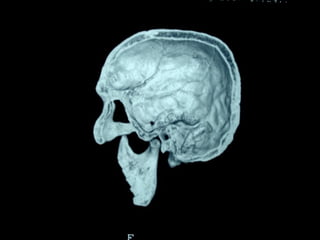

Esclerosis lateral amiotrófica Crouzón